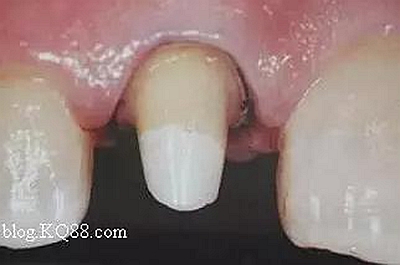

在操作的過(guò)程中要注意無(wú)菌操作,保證纖維樁的無(wú)菌狀態(tài)。推薦將樹(shù)脂核堆好之后再截?cái)嗬w維樁,而不是截?cái)嗪笤僬辰印H缦聢D:

10、排齦精修